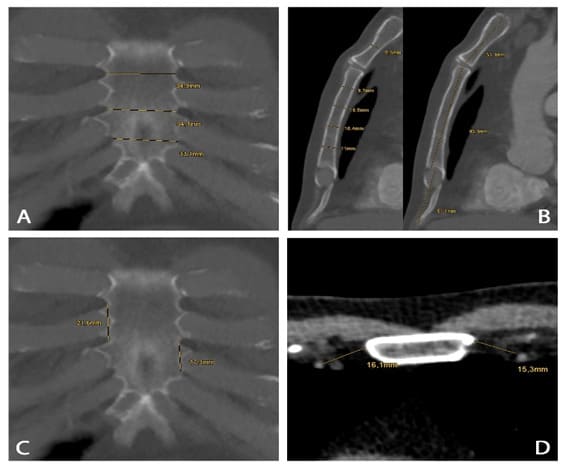

To assess whether the sternal clips reflect the anatomical situation of the sternum, 50 randomly selected CT scans of the thorax between 12/2016 and 02/2017 were used to obtain osteometric data of the sternum, adjacent pairs of ribs, and intercostal spaces as well as the lateral distance to the internal thoracic artery on both sides. Sex, height and weight were determined for the selected patients. The underlying indication for the CT scan was not considered but thoracic trauma was excluded. All CT scans were performed on an 2nd generation dual-source CT system (SOMATOM Flash, Siemens Healthineers, Forchheim, Germany) with intravenous application of iodinated contrast material for visualizing the exact course of the arterial vessel. Multiplanar reconstructions in the transverse, coronal and sagittal planes were prepared from the datasets with a slice thickness of 1 mm. Measurements were conducted on a dedicated workstation (Deep Unity, Dedalus Healthcare Systems Group, Germany). Using sagittal reconstructions, first the maximum length of the manubrium, the sternal body and the xiphoid process were measured in the median line. The widths of the manubrium and sternal body – at the level of the 1st to 5th intercostal spaces (ICS) – were then determined in the coronal reconstruction and the vertical parasternal distances between two ICS were measured. The latter measurements were taken between the 1st and 2nd ICS, the 2nd and 3rd ICS, the 3rd and 4th ICS and the 4th and 5th ICS. Lastly, in transverse slice planes at the level of ICS 1 to 5, the thickness of the sternum and the horizontal distance between the lateral sternum margins and the parasternal course of the internal thoracic artery on both sides were determined at the levels of ICS 1, 2 and 4. Individual measurements are shown as examples in Figure 2.

Figure 2: Exemplary measurements of sternal parameters in CT scans. (A) to (D) show exemplary measurements of sternal parameters using multiplanar reconstructions of randomly selected CT scans: width (A) at the level of 3rd to 5th intercostal space; thickness (B, left) at the level of 1st to 5th intercostal space; length (B, right) of manubrium, corpus and xiphoid process in the median line; vertical parasternal distances (C) between 3rd / 4th and 4th / 5th ICS; parasternal distance of the internal thoracic artery on both sides at the levels of ICS 4.